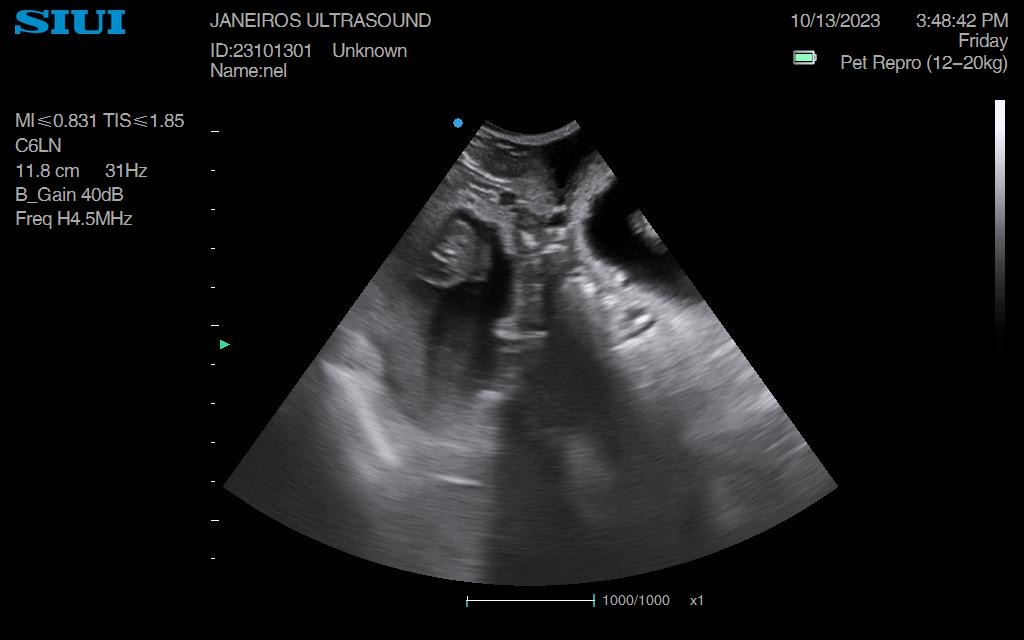

Nel, Dachshund Pregnancy Scan Conisbrough Animal Ultrasound Association Dachshund Ultrasound They are visible on an ultrasound, particularly their little spines. At this stage, the fetuses are about the size of a. Your vet can perform an ultrasound to confirm the pregnancy and check the health of the embryos. The spine and the eyes start to develop, and their faces begin to shape up. The best way to determine if your. Dachshund Ultrasound.

From www.animalultrasoundassociation.org